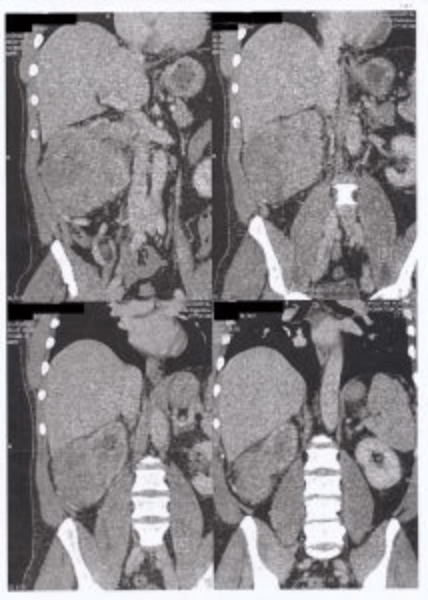

Στον έλεγχο που ακολούθησε στο νοσοκομείο Metropolitan, και τον οποίο ανέλαβε κατόπιν προσωπικής επιλογής του ασθενούς η Ουρολογική Κλινική του Δρ. Βασίλη Πουλάκη, βρέθηκε ένας ευμεγέθης 14,5 εκατοστά όγκος στον δεξιό νεφρό με πολλαπλούς παρααορτικούς λεμφαδένες έως 1,5 εκατοστά βραχείας διαμέτρου ο μεγαλύτερος, επικουρικά ευμεγέθη αγγεία να τροφοδοτούν απευθείας τον όγκο και θρόμβος στην νεφρική φλέβα και στο αρχικό τμήμα της κάτω κοίλης φλέβας.

Ο ασθενής, αφού πρώτα εμβολίστηκε επιτυχώς ο νεφρικός όγκος από τον επεμβατικό Ακτινολόγο Δρ. Γεώργιο Παπαγεωργίου, χειρουργήθηκε ρομποτικά, με το υπερσύγχρονο ρομποτικό σύστημα da Vinci Xi, από τον Δρ. Βασίλη Πουλάκη και τον βοηθό του Δρ. Βασίλη Μώρο. Κατά την διάρκεια της ρομποτικής επέμβασης διενεργήθηκε ριζική αφαίρεση του νεφρού μαζί με τους διογκωμένους επιχώριους λεμφαδένες, ενώ ο θρόμβος του όγκου ήταν στο αρχικό τμήμα της νεφρικής φλέβας αφαιρέθηκε μαζί (en block) με το συνολικό χειρουργικό παρασκεύασμα, με ειδική αγγειοχειρουργική τεχνική (“milking”), επίσης ρομποτικά χωρίς να μετατραπεί το χειρουργείο σε ανοιχτό. Τέλος, κατά την διάρκεια της ρομποτικής επέμβασης, ανευρέθηκαν, στην εξωτερική επιφάνεια του ήπατος που ήταν σε επαφή με τον νεφρικό όγκο, 3 ογκίδια διαμέτρου περίπου 1,5 με 2 εκατοστά, τα οποία δεν μπορούσαν να φανούν στην προεγχειρητική αξονική και μαγνητική τομογραφία. Τα ογκίδια αυτά του ήπατος θεωρήθηκαν ύποπτα ηπατικών μεταστάσεων-εμφυτεύσεων και αφαιρέθηκαν επίσης ρομποτικά από τον Δρ. Βασίλη Πουλάκη.

Η μετεγχειρητική βιοψία έδειξε ότι επρόκειτο για νεφροκυτταρικό καρκίνωμα μέγιστης διαμέτρου 14,5 εκατοστά, το οποίο αφαιρέθηκε πλήρως με αρνητικά χειρουργικά όρια. Ευτυχώς για τον ασθενή τα ογκίδια του ήπατος ήταν καλοήθη αδενώματα και όχι μεταστάσεις από τον καρκίνο του νεφρού.